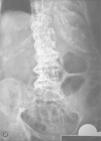

Masa glútea en anciana con enfermedad de Paget del hueso

A. Ballarín González, P. Laguna del Estal, H. de la Torre Martí, J.M. Palau Fayos

Servicio de Medicina Interna. Hospital Universitario Puerta de Hierro. Madrid. España